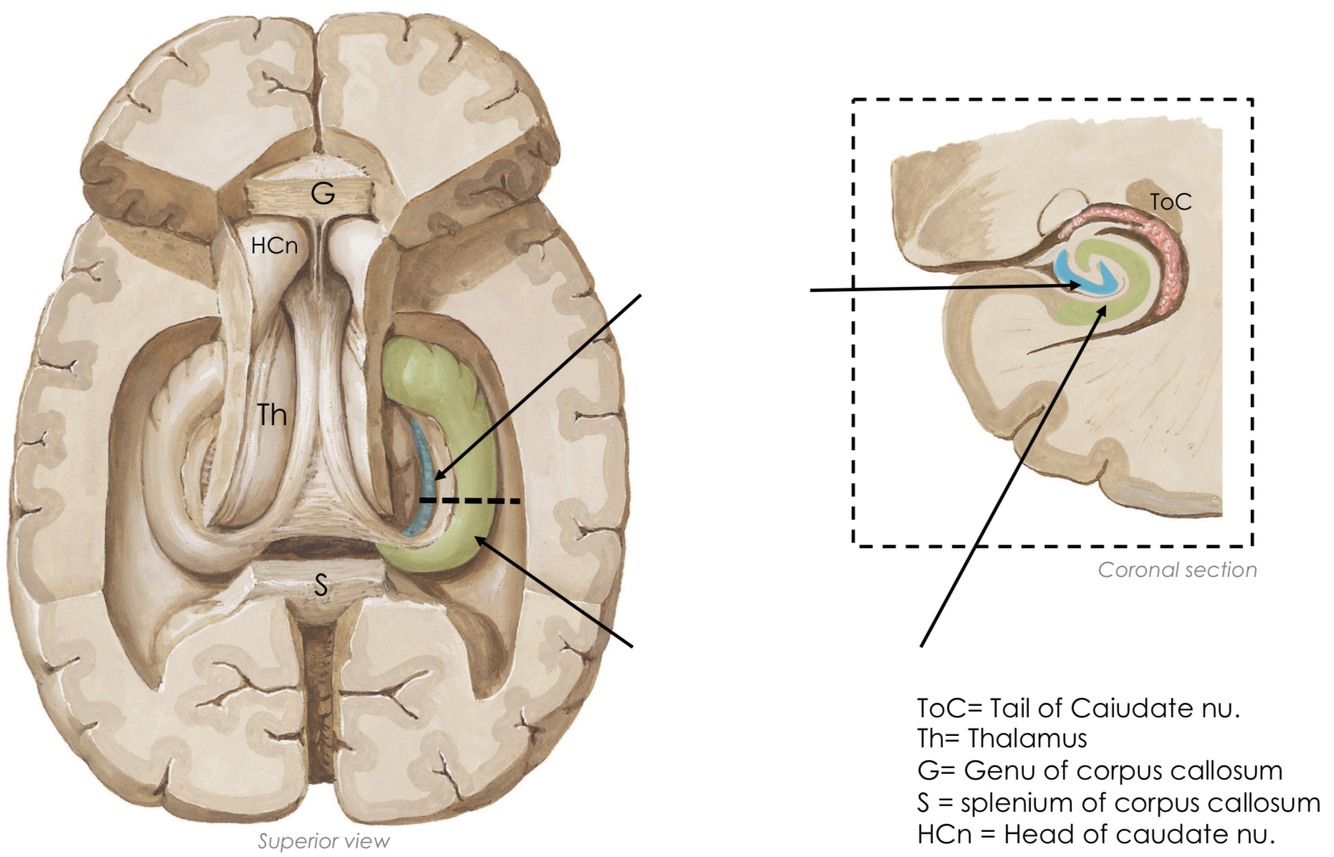

Label the features of the hippocampal formation

What is their appearance like?

Dentate gyrus:

- strip of grey matter with a tooth-like appearance

Hippocampus proper:

- has a seahorse appearance in coronal section

the hippocampal formation forms the floor of the inferior horns of the lateral ventricles